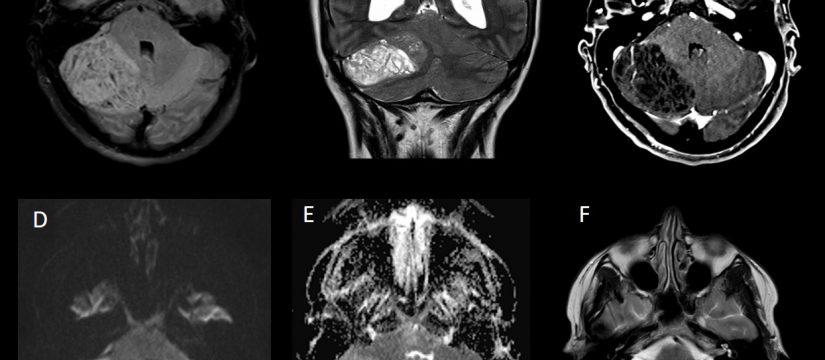

Historia Clínica

Varón de 40 años con esclerosis múltiple remitente-recurrente ya conocida, que consulta por disartria de varios días de evolución.